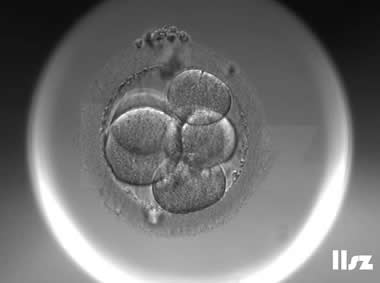

下面视频是胚胎在时差培养箱中培养至D3的整个过程,图片是D3(第68小时)的卵裂期胚胎图,本文D3胚胎评价是以D3时间点图片的形态学为依据,胚胎评级如下:

| Ⅰ级:该枚D3胚胎为8细胞,碎片不超过10%,因此评级为I级。 | |